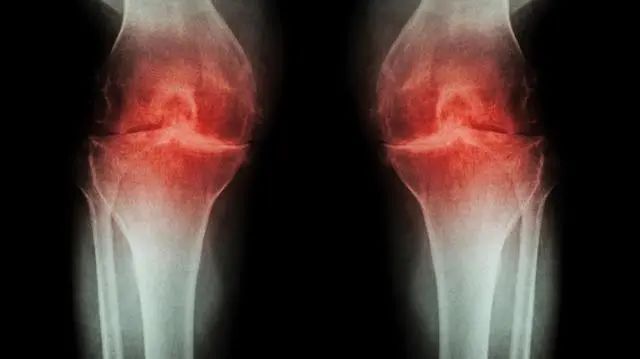

膝关节OA的诊断标准

①一个月里大多数日子膝痛;

②X线关节边缘有骨赘形成;

③OA性滑液(透明、黏性、WBC﹤2000/ml)

④不能查滑液,年龄≥40岁;

⑤晨僵≤30分钟;

⑥关节活动时弹响声。

最少存在①②,或①③⑤⑥,或①④⑤⑥,即可诊断OA。